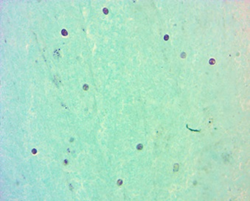

h.1) Resonancia magnética cerebral con corte sagital y secuencia T1 con gadolinio. Se encontró imagen heterogénea, con efecto de masa y zonas de reforzamiento en el interior. (Figura 1).

Figura 1. Resonancia magnética cerebral encorte sagital y secuencia T1 con gadolinio.